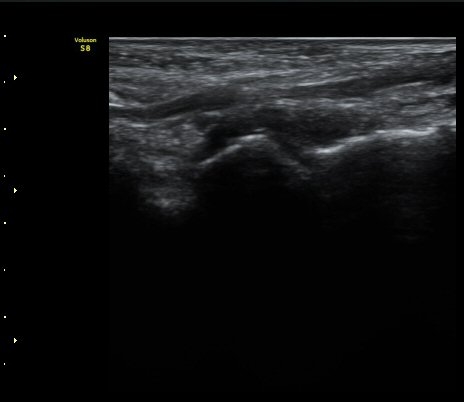

Á¾°ñÀÔ¹æ°ñÀÎ´ë ¿ÜÃø Á¾´Ü¸é°Ë»ç¿¡¼­ ¼ö¾×Àú·ù°¡ °üÂûµÊ(»çÁø 6, 7).